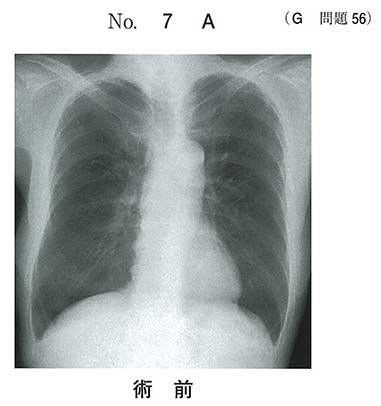

78歳の男性。冠動脈バイパス術直後で手術室に入室中である。未覚醒で人工呼吸中である。脈拍88/分、整。血圧120/80mmHg。動脈血ガス分析(吸入酸素濃度100%):pH 7.30 、PaCO2 50Torr、PaO2 200Torr、HCO3- 24mEq/L。術前と全身麻酔下手術の終了直後の胸部エックス線写真(別冊No.7A、B)を別に示す。